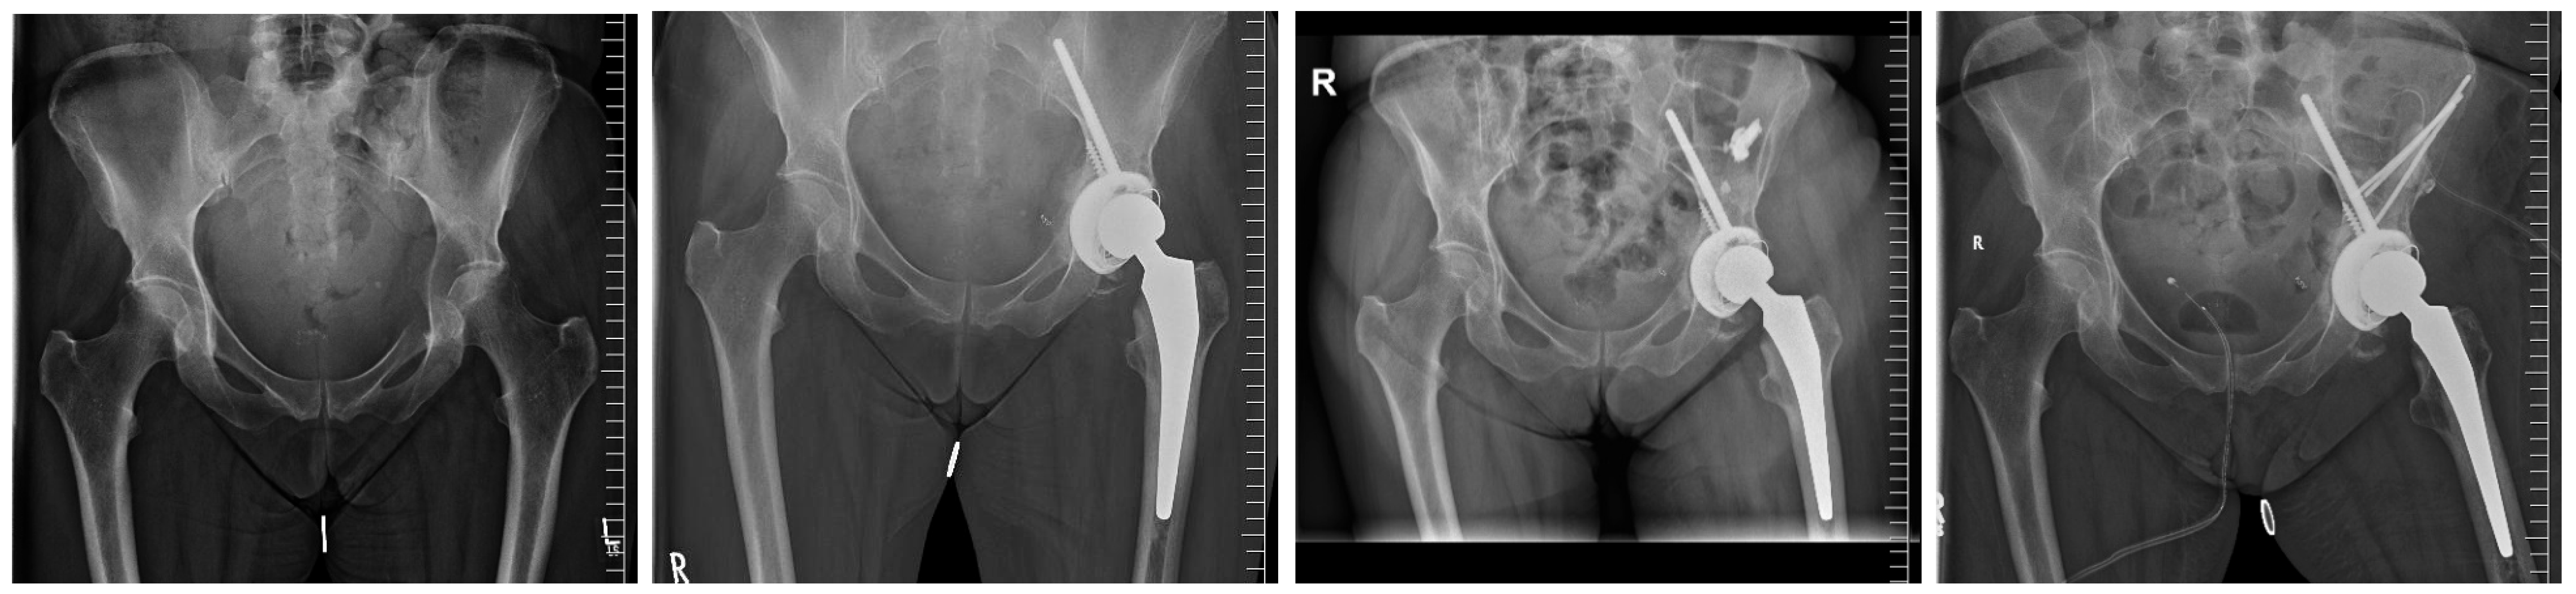

| Overall PRS implant size b (mm) | 56 ± 4 [52–68] |

| Tripolar acetabular systems; n (%) | 6 (50) |

| ->PRS® a implant size b (mm) | 60 ± 4 [56–68] |

| Cemented PE-Cup; n (%) | 6 (50) |

| ->PRS® a implant size b (mm) | 54 ± 2 [52–56] |

| Modular metal augments; n (%) | 2 (17) |

| Number of additional fixation screws b | 3 ± 1 [2–7] |

| Added screw lengths (mm) b | 161 ± 56 [100–290] |

| Lengths of 8 mm screw (mm) b | 90 ± 10 [70–100] |

| Added lengths of solely 6 mm screws (mm) b | 71 ± 56 [0–100] |